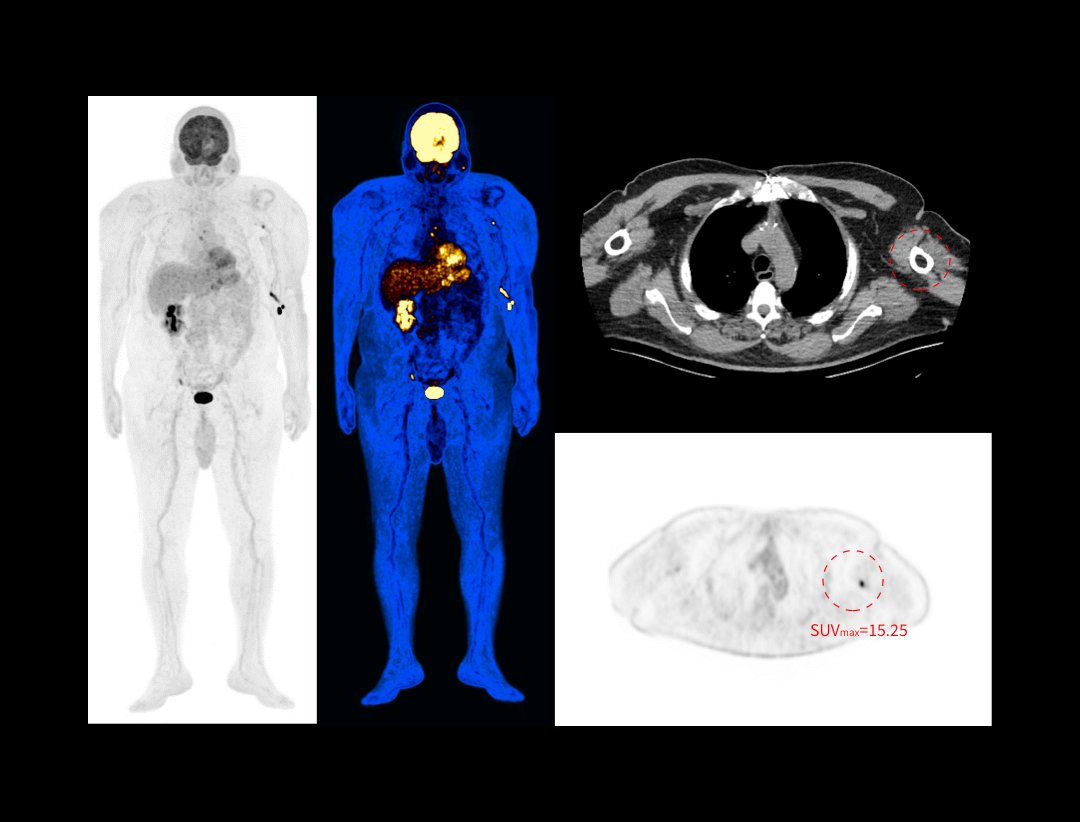

With the unique Integrated-Light-Guide Digital PET technology and a 160-slice CT system, uMI Vista combines high quality functional images with fine anatomical structure visualization. The state-of-the-art reconstruction technology and comprehensive applications further boost diagnostic precision in oncology, neurology and cardiology.

2.9mm NEMA Resolution

Outstanding resolution performance is achieved through systematic imaging chain engineering.

HYPER Iterative Reconstruction

Improves signal-to-noise ratio and contrast recovery to aid lesion detectability and quantitative accuracy.